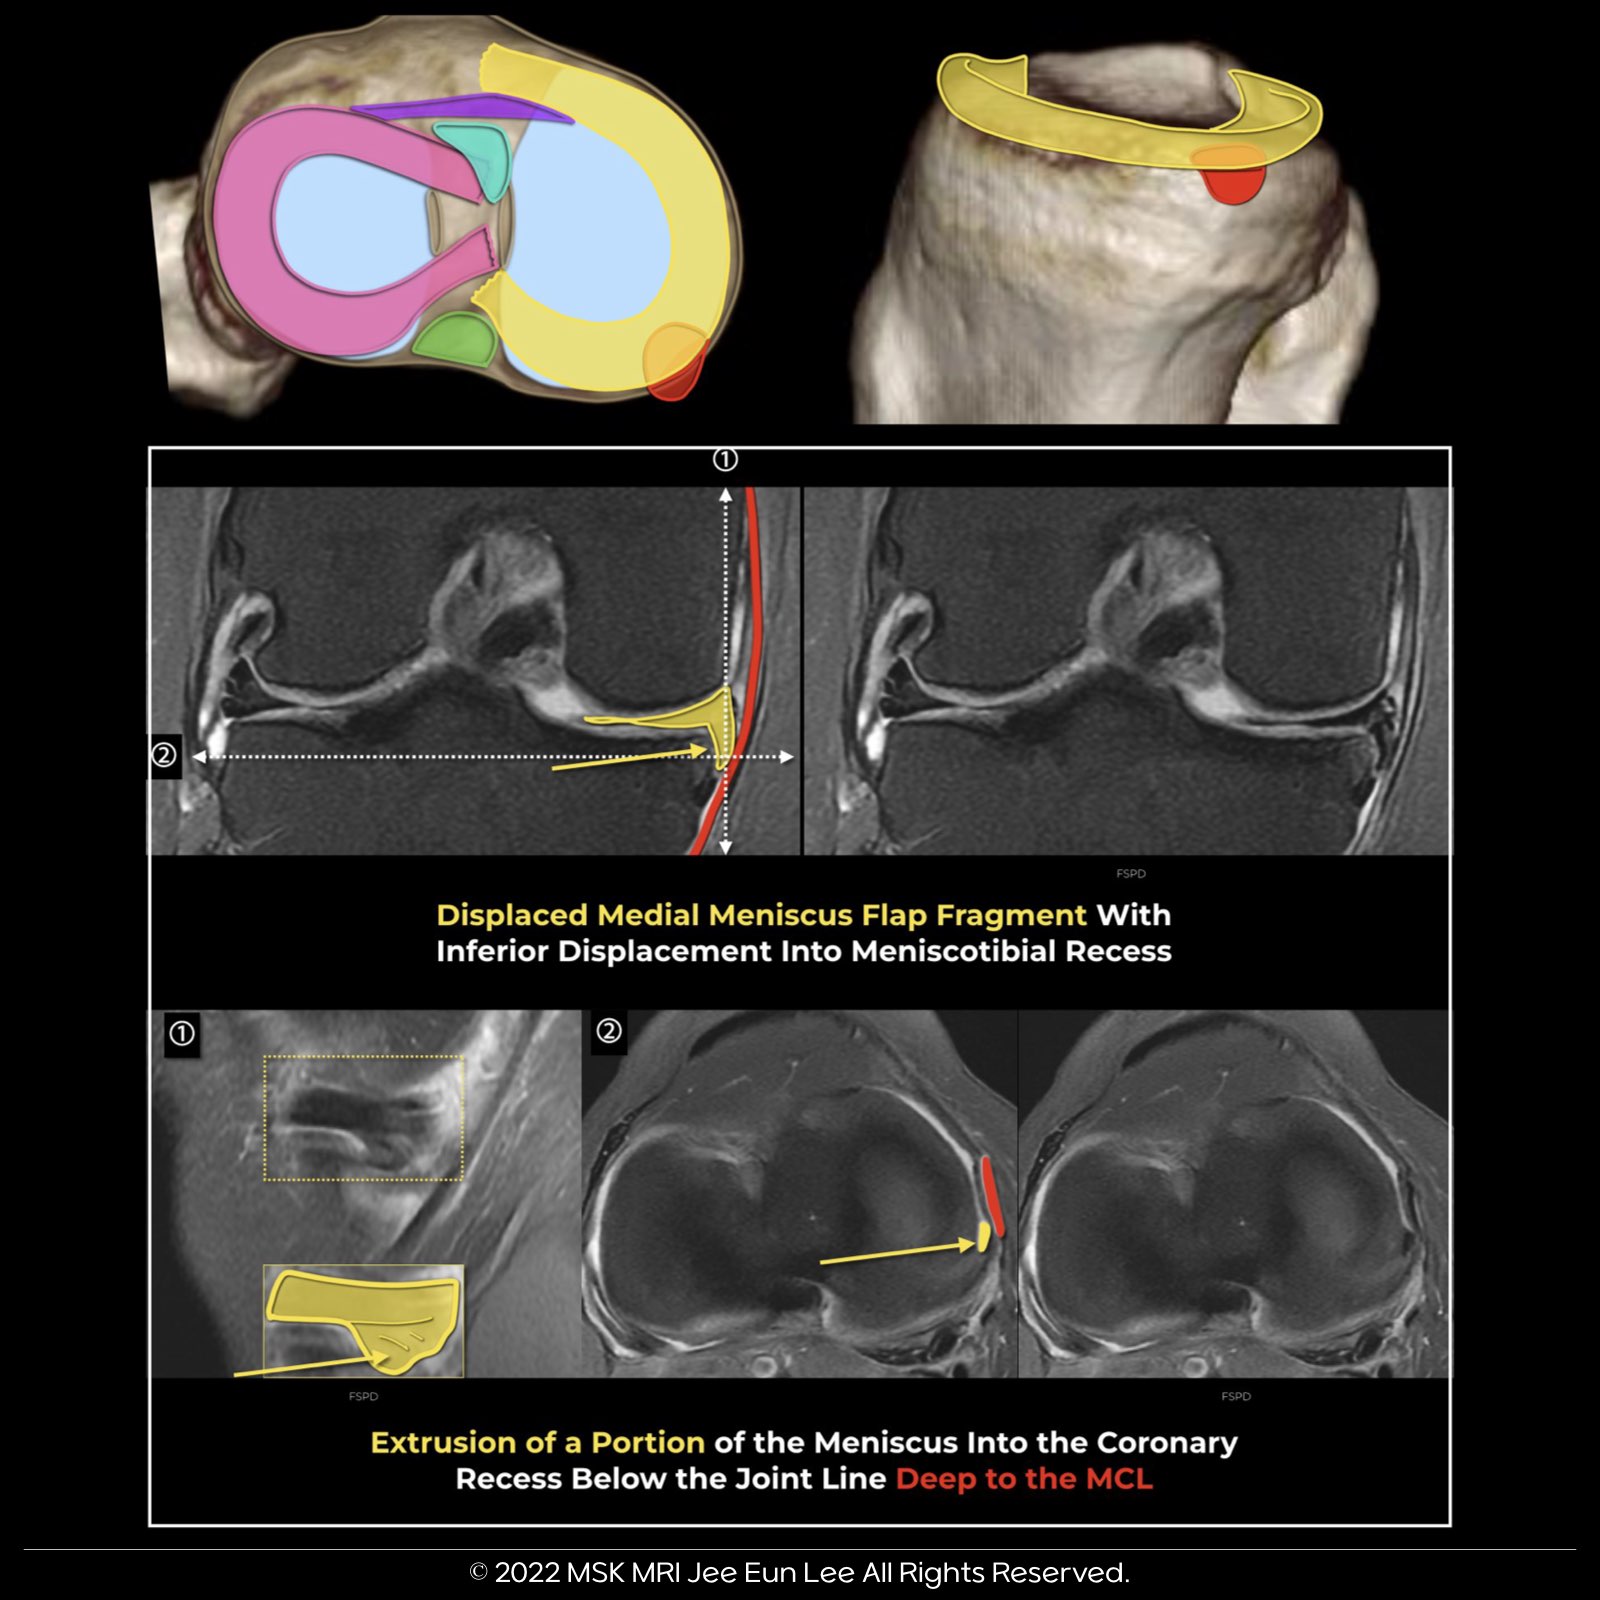

Insight into Horizontal Flap Tears of the Meniscus

What Are Horizontal Flap Tears?

- Horizontal flap tears involve a short segment of the meniscus with the displacement of a meniscal leaf.

- These tears commonly result in the displacement of the meniscal fragment, usually found in the posterior intercondylar notch or the gutters.

Patterns of Displacement:

- For medial meniscus tears, 93% of fragments are located medially or posterolaterally, commonly in the superior or inferior recesses.